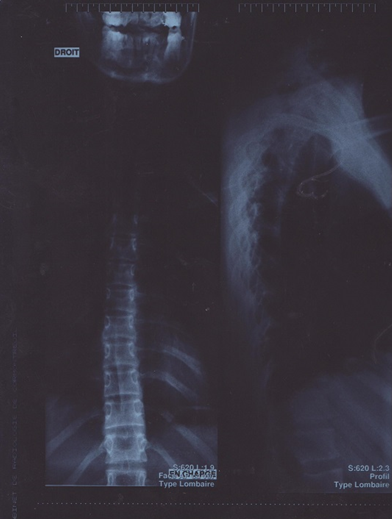

- Radiographies